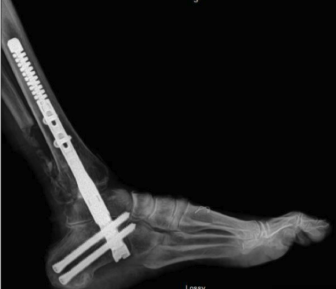

Tibiotalocalcaneal (TTC) Fusion

Hindfoot arthrodesis involves removing damaged cartilage from the affected joints and positioning the bones in optimal alignment. The joints are then stabilized using screws, plates, or other fixation devices to allow the bones to fuse together.